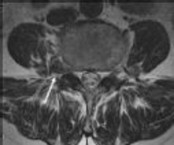

low back pain and fever. His blood cultures are positive for methicillin-resistant Staphylococcus aureus (MRSA). He has no neurologic signs or symptoms of lumbar radiculopathy or cauda equina syndrome. Figure 1 shows his axial T2-weighted MRI, and an arrow marks the junction of the theca sac and the epidural abscess. What is the most appropriate recommendation for this patient?

4. Anterior diskectomy, followed by antibiotics Discussion: C

Epidural abscess once was considered an absolute indication for surgery. Nonsurgical management has been gaining ground for select patients, however. Kim and associates reported the results of a large series of patients treated for epidural abscess. Many of the patients were treated successfully without surgery, and nonsurgical management was chosen for many of the patients who presented without signs or symptoms of neurologic dysfunction. The authors identified four risk factors that were highly associated with the failure of nonsurgical management, however, including age older than 65 years, diabetes, MRSA, and neurologic compromise.